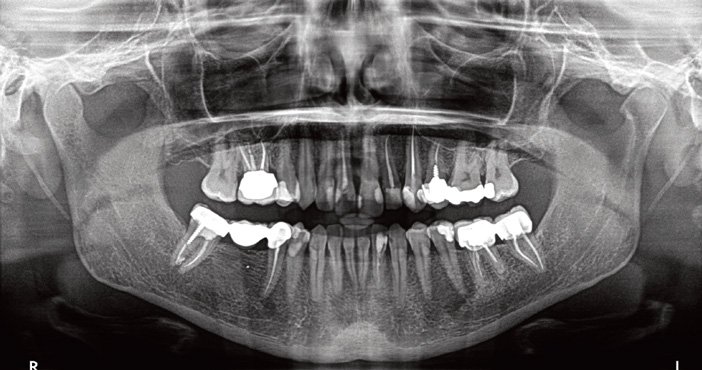

Le problème : Lors de la présentation d’un cas radiologique de fracture mandibulaire, certains étudiants ne distinguent pas clairement les fractures du corps, de l’angle et de la branche montante.

La conséquence : Erreur de classification, mauvaise compréhension des traitements appropriés.

La bonne pratique : Identifiez systématiquement les zones anatomiques sur le panoramique : corps (entre symphyse et angle), angle mandibulaire, branche montante, condyle/sous-condylaire, apophyse coronoïde. Chaque localisation a sa propre prise en charge.

Problématique : Sur le panoramique dentaire, on observe un déplacement du condyle gauche sans enfoncement dans la fosse temporale. Le diagnostic de fracture sous-condylienne gauche est posé.

Rappel anatomique : Le col du condyle, zone de jonction entre le condyle et la branche montante, est la zone de moindre résistance mécanique de la branche montante. Chez l’enfant, la mandibule encore en croissance présente un os moins compact et plus susceptible aux fractures en ce point.

Problématique : Lors de la lecture du panoramique préopératoire, le canal dentaire inférieur semble proche des crêtes alvéolaires. Un cone beam est prescrit : il révèle une distance nerf-crête de seulement 7 mm en regard du site 36, avec un trajet sinueux du canal.

Quelles sont les fractures les plus fréquentes de la mandibule ?

Par ordre de fréquence, on trouve : les fractures condyliennes et sous-condyliennes (30 à 36 % des cas), les fractures de l’angle mandibulaire (souvent liées aux 3es molaires incluses), et les fractures parasymphysaires. Les fractures condyliennes sont particulièrement fréquentes chez l’enfant, en raison de la vulnérabilité du col du condyle lors des traumatismes en compression axiale (chute sur le menton).